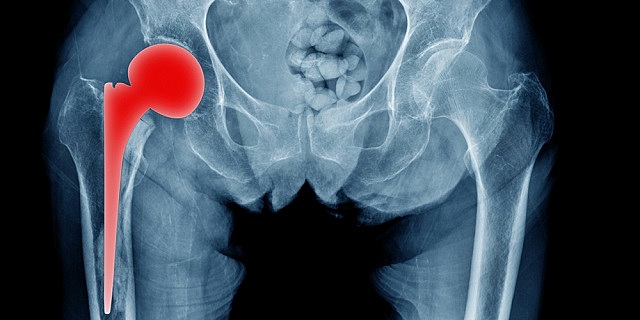

• Actualidad de la artroplastia

Actualidad de la artroplastia

Vástago ha pasado de acero a aleaciones de cromo – cobalto y titanio.

Cabeza femoral se ha pasado de acero a cromo – cobalto y cerámicos.

Se busca eliminar el uso del cemento para la fijación de los componentes protésicos introduciendo nuevas técnicas de fijación como son el bloqueo mecánico y el recubrimiento de los componentes con hidroxiapatita para intentar que el tejido óseo se una químicamente a la hidroxiapatita, y que sea dicha unión la que produzca la fijación del implante.